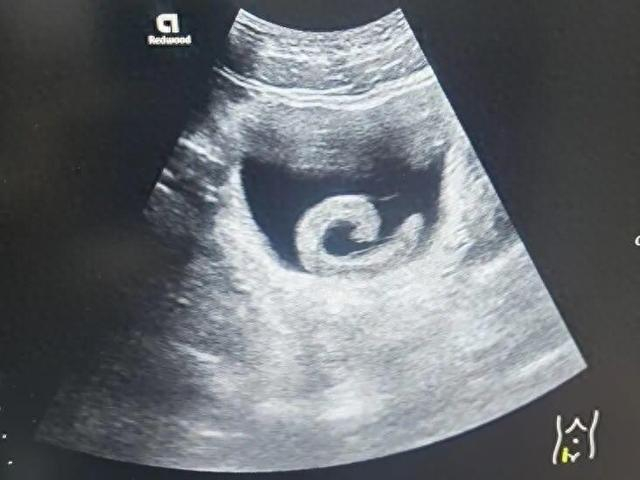

泌尿外科副主任医师马曜辉为小郑实施了经尿道膀胱异物取出术,手术顺利,小郑的尿道梗阻解除疼痛瞬间消失,但回想起自己的所作所为,他只剩后怕和悔恨。

泌尿外科主任单中杰表示:“这绝不是个案,类似将异物塞入尿道的患者,我们每年都会接诊数例。手术本身有风险,且对尿道和膀胱可能造成二次损伤。可能遗留慢性疼痛、排尿功能障碍反复感染、尿道狭窄等长期痛苦。”